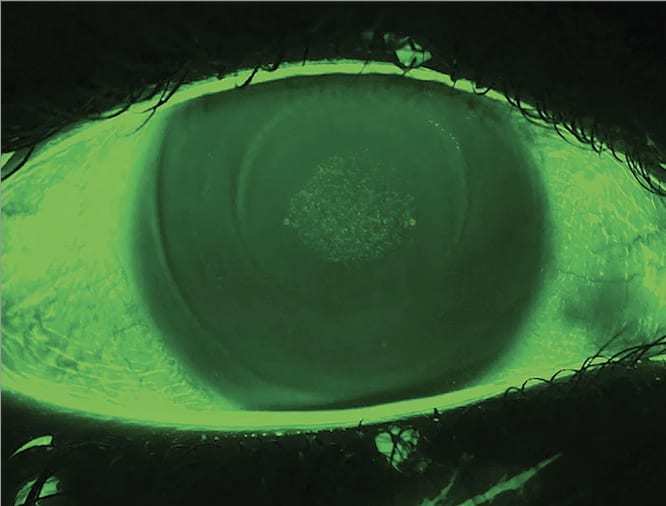

Practice Tip: Manage Contact Lens Related Dry Eye in Orthokeratology Patients

“As is the case with all contact lens wear, it’s important for prescribers to be aware of contact lens-related dry eye in orthokeratology wearers, so patients can maintain wear,” writes Dr. Maria Liu in her latest “Myopia” column. One way to achieve this: Ensure proper lens fit, as suboptimal lens fit is the primary cause of ocular dryness from ortho-k lens wear among children, she points out. Read more